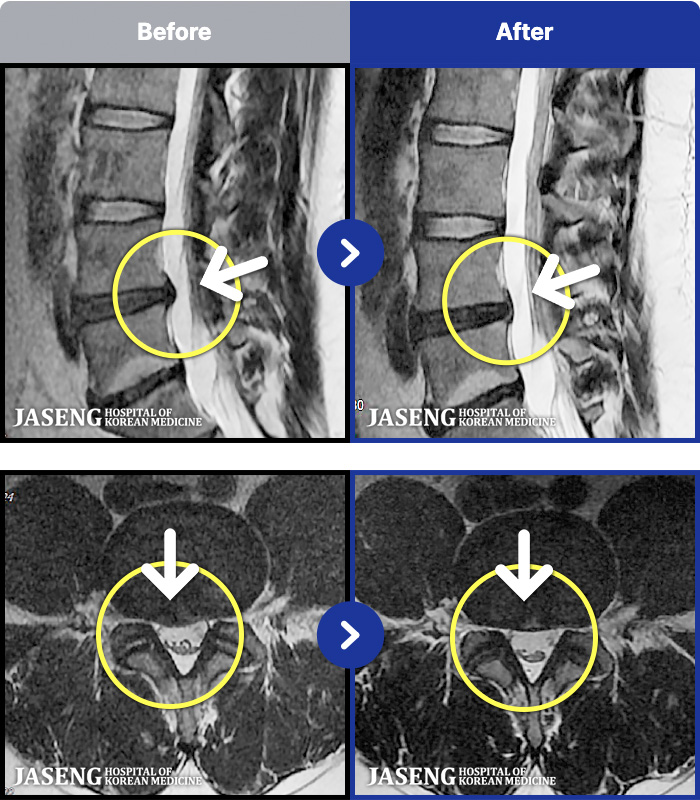

ȯںп Ǹ ǿ ԿǾ, ο ġ ۿ Ƿ ġḦ Ͻñ ٶϴ.